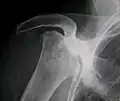

-

Radiography of total avascular necrosis of right humeral head. Woman of 81 years with diabetes of long evolution. -